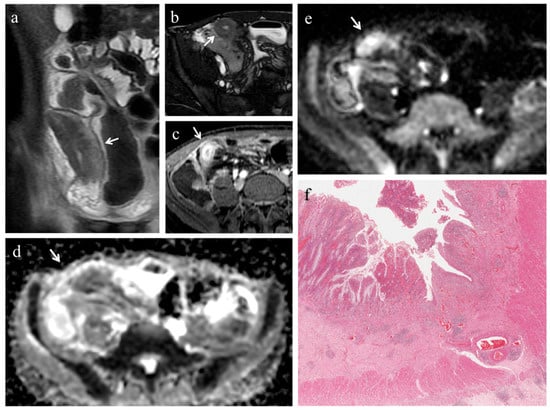

Figure 3. (ae). MRE in a 22-year-old man with CD: predominantly inflammatory stricture of the terminal ileum. (a) Coronal FIESTA image shows mural thickening of terminal ileum with stenosis of the lumen (white arrow). (b) Coronal contrast-enhanced fat-suppressed T1-weighted image demonstrates the homogeneous wall enhancement of the affected ileal loop. The same intestinal segment demonstrates restricted diffusion in the form of high signal intensity on (c) the DW image (b = 800 s/mm2) and low signal intensity on (d) the corresponding ADC map (white arrows) (mean ADC value 1.320 × 10−3 mm2/s). (e) Histopathological section from the ileal stricture: hematoxylin and eosin-stained sample (H&E 10×). CD exhibiting absent or minimal fibrosis (FS = 0) and severe inflammation (AIS = 9): mucosal ulceration and intense inflammatory infiltration on the top; edema and intense inflammatory infiltration in the submucosal layer.

In 18 (78.3%) ileal segments, inflammation and fibrosis coexisted (Figure 1 and Figure 2), in 5 (21.7%) cases inflammatory alterations without fibrosis were found (Figure 3), whereas under no circumstances was fibrosis without inflammation encountered. No significant correlation was highlighted between AIS and FS (p = 0.22).

Pattern of enhancement. The diseased bowel wall showed the following enhancement patterns: homogeneous in 6 cases (26.1%) (Figure 1b,c, Figure 3b), mucosal in 8 cases (34.8%) (Figure 2c) and layered in 9 cases (39.1%). Pattern of enhancement did not show significant variations according to AIS (p = 0.56) or FS (p = 0.49).

Pre-stenotic luminal diameter. Maximum caliber of pre-stenotic upstream bowel (mean 33 ± 14 mm, range 17–80 mm) did not correlate with inflammation score (p = 0.50). On the other hand, pre-stenotic bowel dilatation positively correlated with the fibrosis score (p = 0.002): upstream bowel dilatation increased according to fibrosis grade (Figure 1a). In particular, pre-stenotic luminal diameter was higher in patients with severe fibrosis than in those with none or mild/moderate fibrosis (p < 0.05) (Figure 4, Panel a). The mean pre-stenotic luminal diameters were 25 ± 4 mm, 27 ± 5 mm and 47 ± 18 mm for none, mild/moderate and severe FS, respectively. Moreover, this measurement showed a high accuracy (AUC 0.75, p < 0.001) for discriminating between none and mild/moderate–severe bowel wall fibrosis; using a threshold value of 30 mm, the sensitivity and specificity were 100% and 44%, respectively (Figure 5, Panel a).

3.4. Analysis of DWI Quantitative Measures (ADC)

The mean size of the ROIs used to measure the ADC value in the diseased bowel wall was 48 ± 22 mm2. The overall mean of ADC values was 1.168 ± 0.181 × 10−3 mm2/s (range 0.745–1.473 × 10−3 mm2/s). No significant correlation was found between ADC and inflammation score (p = 0.41). The ADC value was negatively correlated with the fibrosis score (p < 0.001). The ADC value was different between FS grades (p < 0.05) (Figure 4, Panel b). The means of the ADC values were 1.371 × 10−3 mm2/s for none, 1.224 × 10−3 mm2/s for mild/moderate and 0.936 × 10−3 mm2/s for severe FS. ADC values showed a high accuracy (AUC 0.97, p < 0.001) for discriminating between none and mild/moderate–severe bowel wall fibrosis. Using a threshold ADC value of 1.300 × 10−3 mm2/s, the sensitivity and specificity were 80% and 100%, respectively (Figure 5, Panel b). Qualitative and quantitative MRE findings are summarized in Table 3.